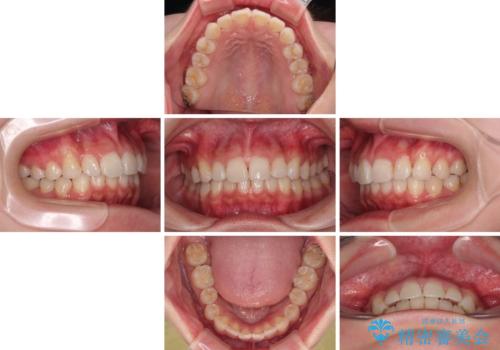

前歯の捻れを改善するとともに、口元が少しでも引っ込むように治療計画を立て、仕上げることができました。

長時間の装着を徹底し、遠方からの通院にもかかわらずしっかりと通院いただき、予想よりも早く治療を終えることができました。